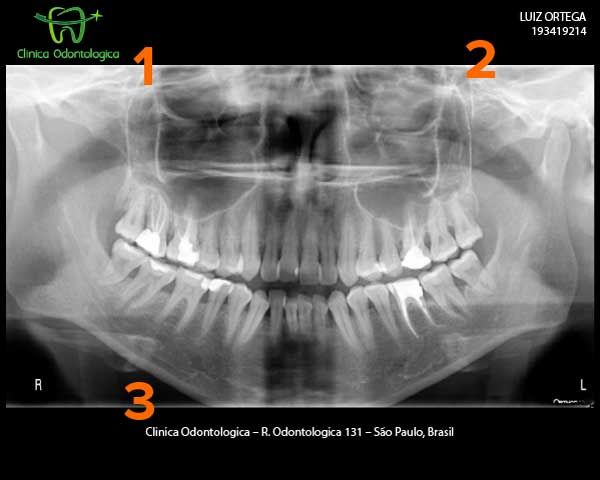

To print true-size images of dental X-rays, with a facility logo in the corner of the film.

We're looking to create output like this:

Note that:

- There is a logo at the top left

- Patient information is displayed at the top right

- Clinic information appears at the bottom